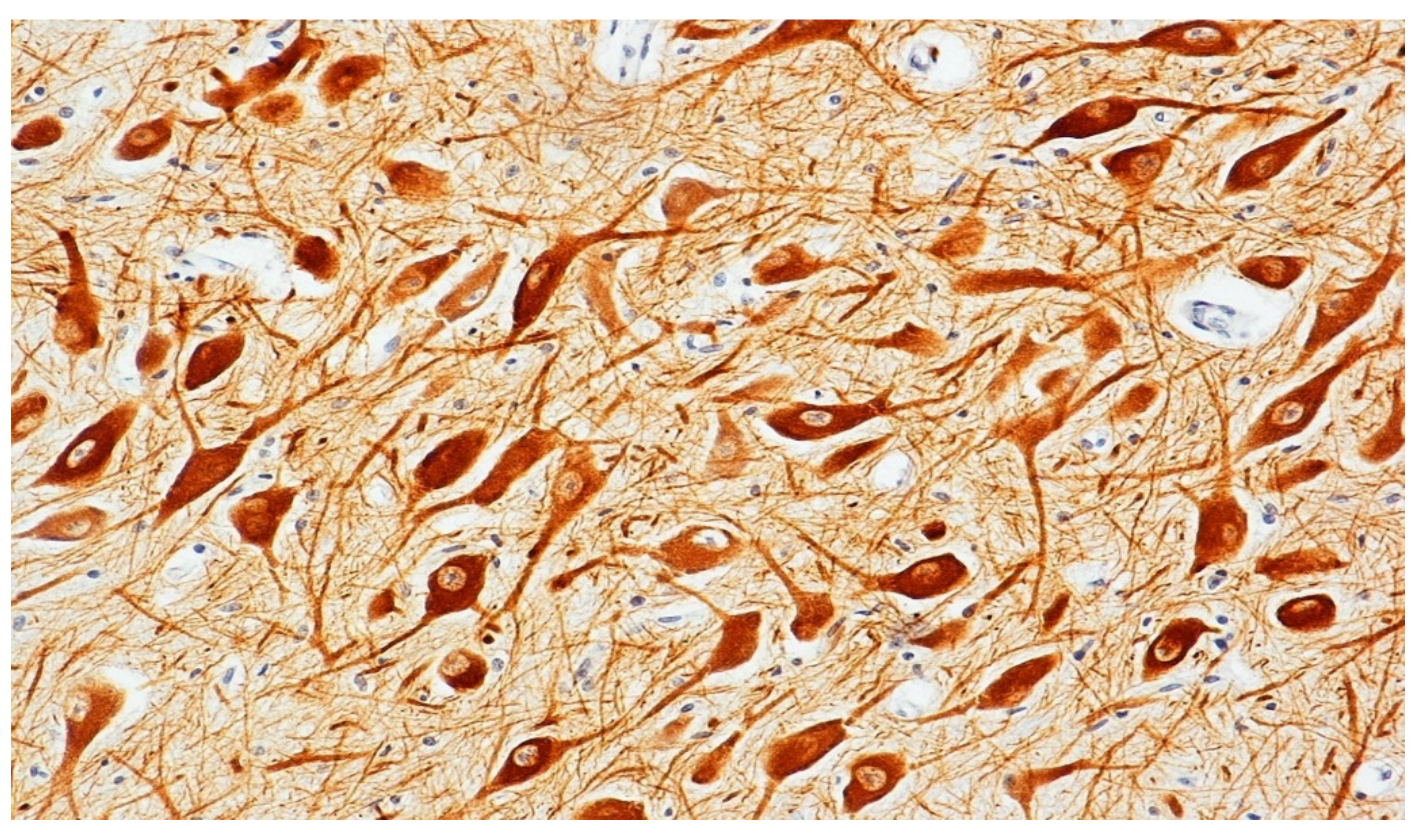

3.1. Immunohistochemical Analysis of the Mesencephalic Dopaminergic (mDA) Neurons in SIDS and Controls

3.1.1. Control Group

3.1.2. SIDS Group

2.5. Immunohistochemical Analysis of Tyrosine Hydroxylase (TH) and Dopamine Transporter (DAT)

Quantification of TH and DAT Immunohistochemical Results